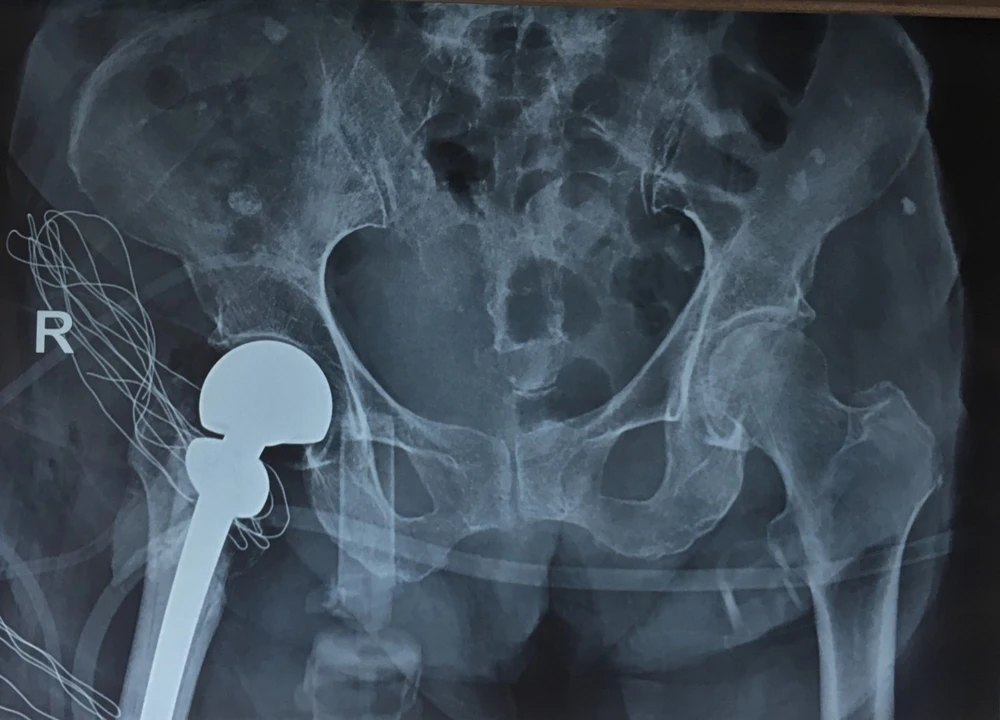

Khớp háng đã được thay mới. Ảnh: BVCC

Tuy nhiên, ca mổ thay khớp háng bán phần chuôi dài có xi măng đã thành công. Hiện tại bệnh nhân đã có thể ngồi dậy, tập theo các động tác trị liệu…